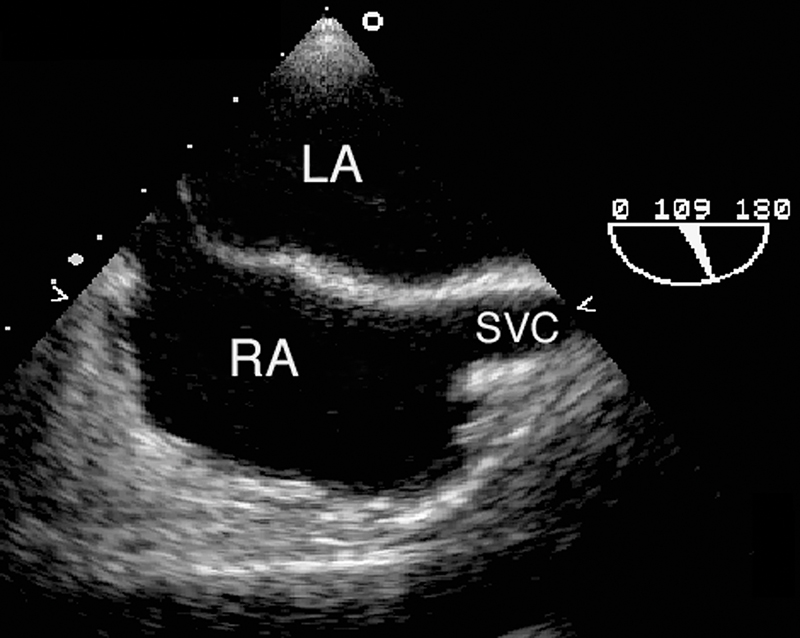

فحوصات تشخيصية لبعض امراض القلب والشرايين التاجية